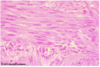

Smooth Muscle